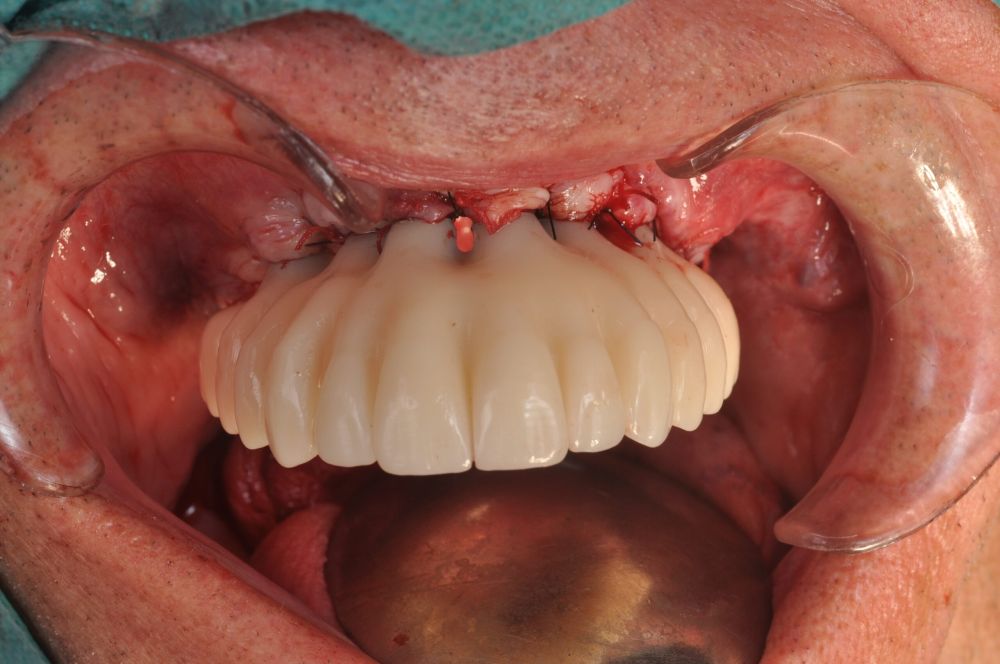

The surgical procedure was performed under general anaesthesia and nasotracheal intubation. A supracrestal incision and detachment of a maxillary flap of total thickness was made (Figures 9 and 10). The boundaries of the dissection were both infraorbital ridges, both laterally malar bodies and the anterior half of the hard palate caudally. In addition, a customized cutting guide was used so that the SI was completely in direct contact with the bone (Figure 11) and the mesh was fixed with the different 1.5 mm osteosynthesis screws in the nasal and zygomatic buttresses (KLS Martin, Freiburg, Germany) (Figure 12). The closure was performed with nonresorbable suture. Finally, the PMMA provisional rehabilitation was screwed for the immediate load, with a torque of 20 N on the implants (Figures 13-15).

Two months later, with the soft tissues healed around the connections (Figure 16), a new intraoral scanning was made of the implants and the provisional prosthesis for future restoration. A FRI type passivity test (rigid impression splint) was manufactured with an aluminium structure to assess the correct fit on the implants (Figure 17). For implant-supported rehabilitation, a sintered structure was made in chrome-cobalt with machined bases covered with acrylic resin teeth from Bredent® (Figures 18-21).